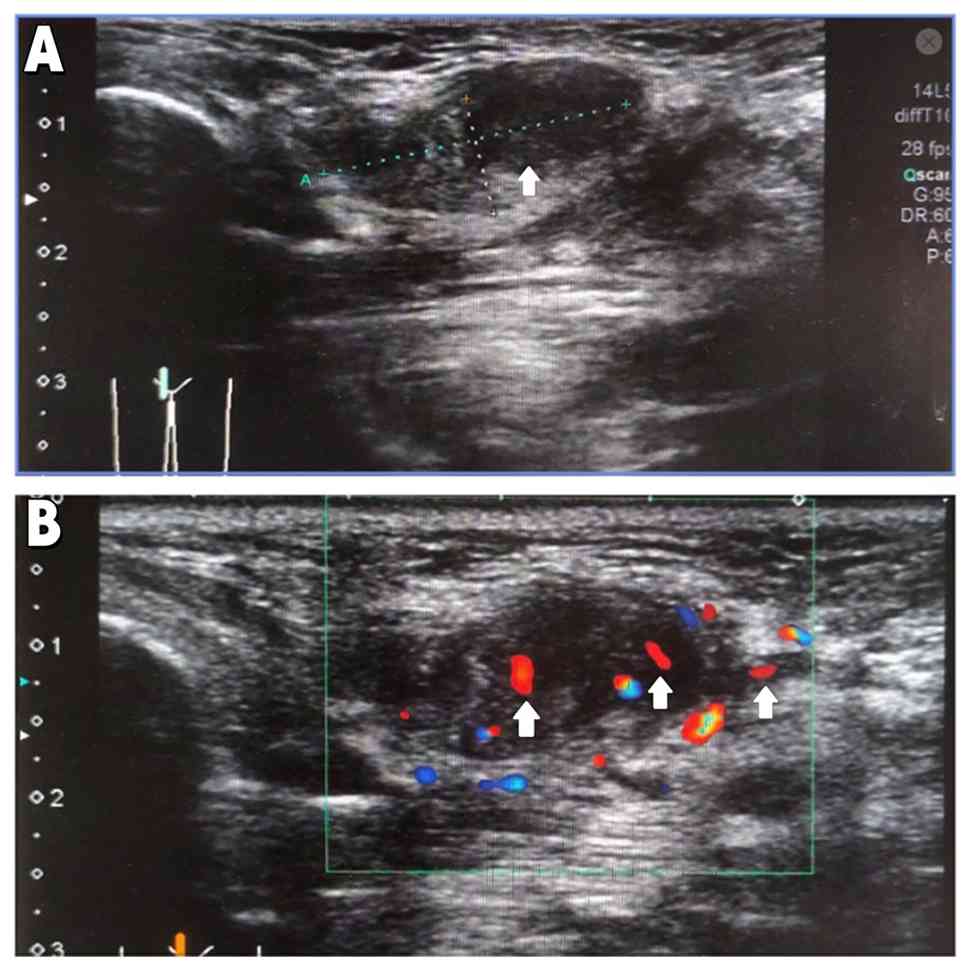

The patient was a 45-year-old Chinese female who underwent regular physical examinations and had no notable past medical history., with menarche at 13 years, having had five pregnancies and one delivery, and with no family history of disease, smoking or drinking. The patient presented with a subcutaneous mass in the right vulvar area that had slowly enlarged over 4 months without pain. The patient had sought medical attention at Central Hospital, Tianjin University in January 2025, due to continuous pain from the mass for 3 days. Upon examination, the skin showed no damage, redness or swelling. Gynecological examination revealed a subcutaneous mass on the right vulva, measuring ~2×1 cm in size. The mass was hard in texture, with mild tenderness and unclear boundaries. As a vestibular gland cyst could be excluded due to clearly defined boundaries, further examination of the patient was conducted. The patient was negative of human papillomavirus (HPV) and tested positively for syphilis. Alanine aminotransferase (ALT) was 30 U/l and aspartate aminotransferase (AST) was 25 U/l, with the normal reference range for both typically being 0–40 U/l. Total bilirubin (TBIL) was 10 µmol/l (normal reference range of <34 µmol/l. Serum creatinine (Cr) was 50 µmol/l, with a normal reference range for females of 44–97 µmol/l. Blood urea nitrogen (BUN) was 7 mmol/l, with a normal reference range typically being 2.9–8.2 mmol/l. Carbohydrate antigen 125 (CA125) was 10 U/ml (reference range typically <35 U/ml. Ultrasound examination showed a heterogeneous echogenic nodule measuring 2.4×1.4×0.9 cm, subcutaneously located on the right vulva, which had uneven internal echoes and blood flow signals visible on the inner edge (Fig. 1). Due to the presence of pain, hard texture, uneven ultrasound echoes and visible blood flow signals, malignancy could not be excluded. The patient underwent surgery on the following day after the initial consultation. The procedure performed was extended local excision. The specific operational steps were as follows: Under local anesthesia, the surgeon excised the lesion along with a surrounding margin of normal tissue using an electrosurgical knife to ensure negative surgical margins. The entire procedure lasted 1 h and 10 min. The resected tissue specimen was sent for pathological examination.

Ultrasound examination (A)

Ultrasonography showed a 2.4×1.4×0.9 cm inhomogeneous echogenic

nodule (arrow), subcutaneously located on the right vulva. (B)

Internal echo was uneven and dot-and-strip blood flow signals

(arrow) were visible at the inner edge.

Ultrasound examination (A) Ultrasonography showed a 2.4×1.4×0.9 cm inhomogeneous echogenic nodule (arrow), subcutaneously located on the right vulva. (B) Internal echo was uneven and dot-and-strip blood flow signals (arrow) were visible at the inner edge.